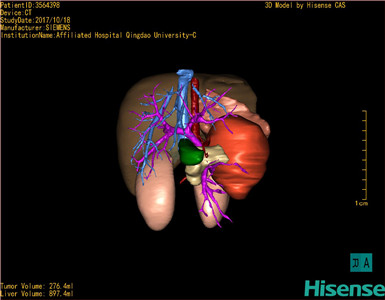

CT结果输入海信CAS系统后行3D重建及手术规划后,于2017-10-19全麻下行“胰体尾肿物切除术+脾切除术+大网膜切除术”手术治疗:

术前三维重建及手术方案设计:

将0.625mm双源薄层CT资料的静脉期和动脉期Dicom格式文件导入海信CAS系统。

通过调节窗宽窗位调整CT序号,对肝实质,胆囊,下腔静脉,肿瘤,肝动脉、门静脉及肝静脉等进行三维重建;系统自动计算肝脏体积。

模拟手术操作,自动计算切除肿瘤体积。肝脏体积为453.7ml,通过比对2-3岁正常肝脏体积为475.97±99.7ml,通过术前模拟手术,精准判断切除后剩余肝脏体积能耐受,避免肝衰竭发生。

术前三维重建:

重建图片